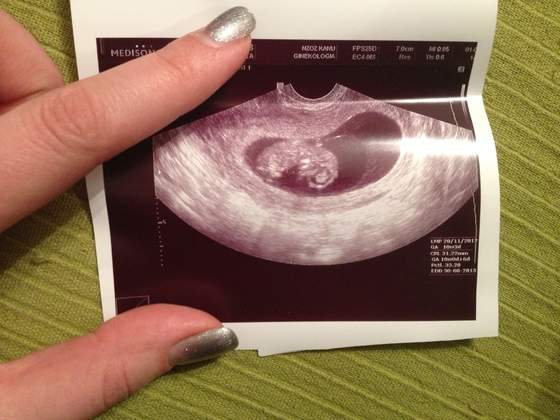

a jesli zas chodzi o wizyte. moj ogromny czlowiek ma 31 mm

machal lapeczkami, i gdzies tam noga fikal heheh, ale sie doktor smial ze lezy twarza w dol hehe w stylu "nie moge na to patrzec"... wg USG Malenstwo ma 10 tygodni rowne, takze roznica tylko 3 dni. sluchalam serduszka, gin powiedzial, ze nagra mi nastepnym razem.